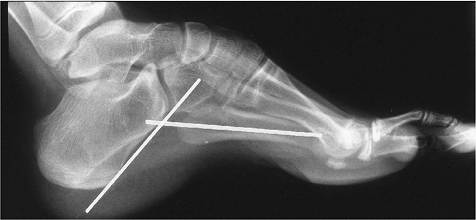

![]() |

FIGURE 6-83 Normal simulated weight-bearing views of the pediatric foot. Normal AP (A) and lateral (B) talocalcaneal angles are 28 degrees (range 25–55 degrees) and 47 degrees (range 25–55 degrees), respectively.

FIGURE 6-84

FIGURE 6-85

FIGURE 6-86 Longitudinal plantar arch angle measured by lines at the calcaneus and fifth metatarsal. Normal 150 to 170 degrees.